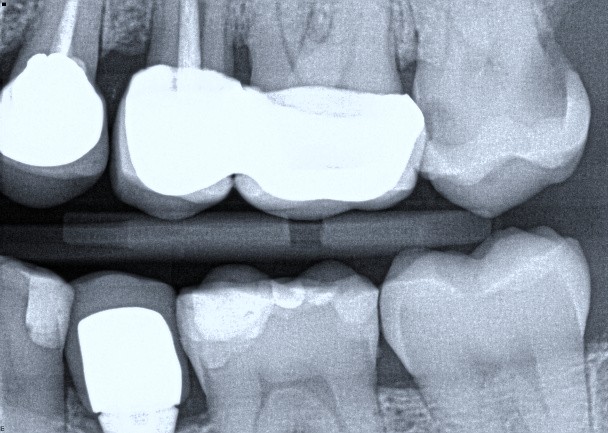

The radiograph shows evidence of

Which of the following is/are seen in the radiograph?

Which of the following is/are seen in the radiograph for tooth 3.6?